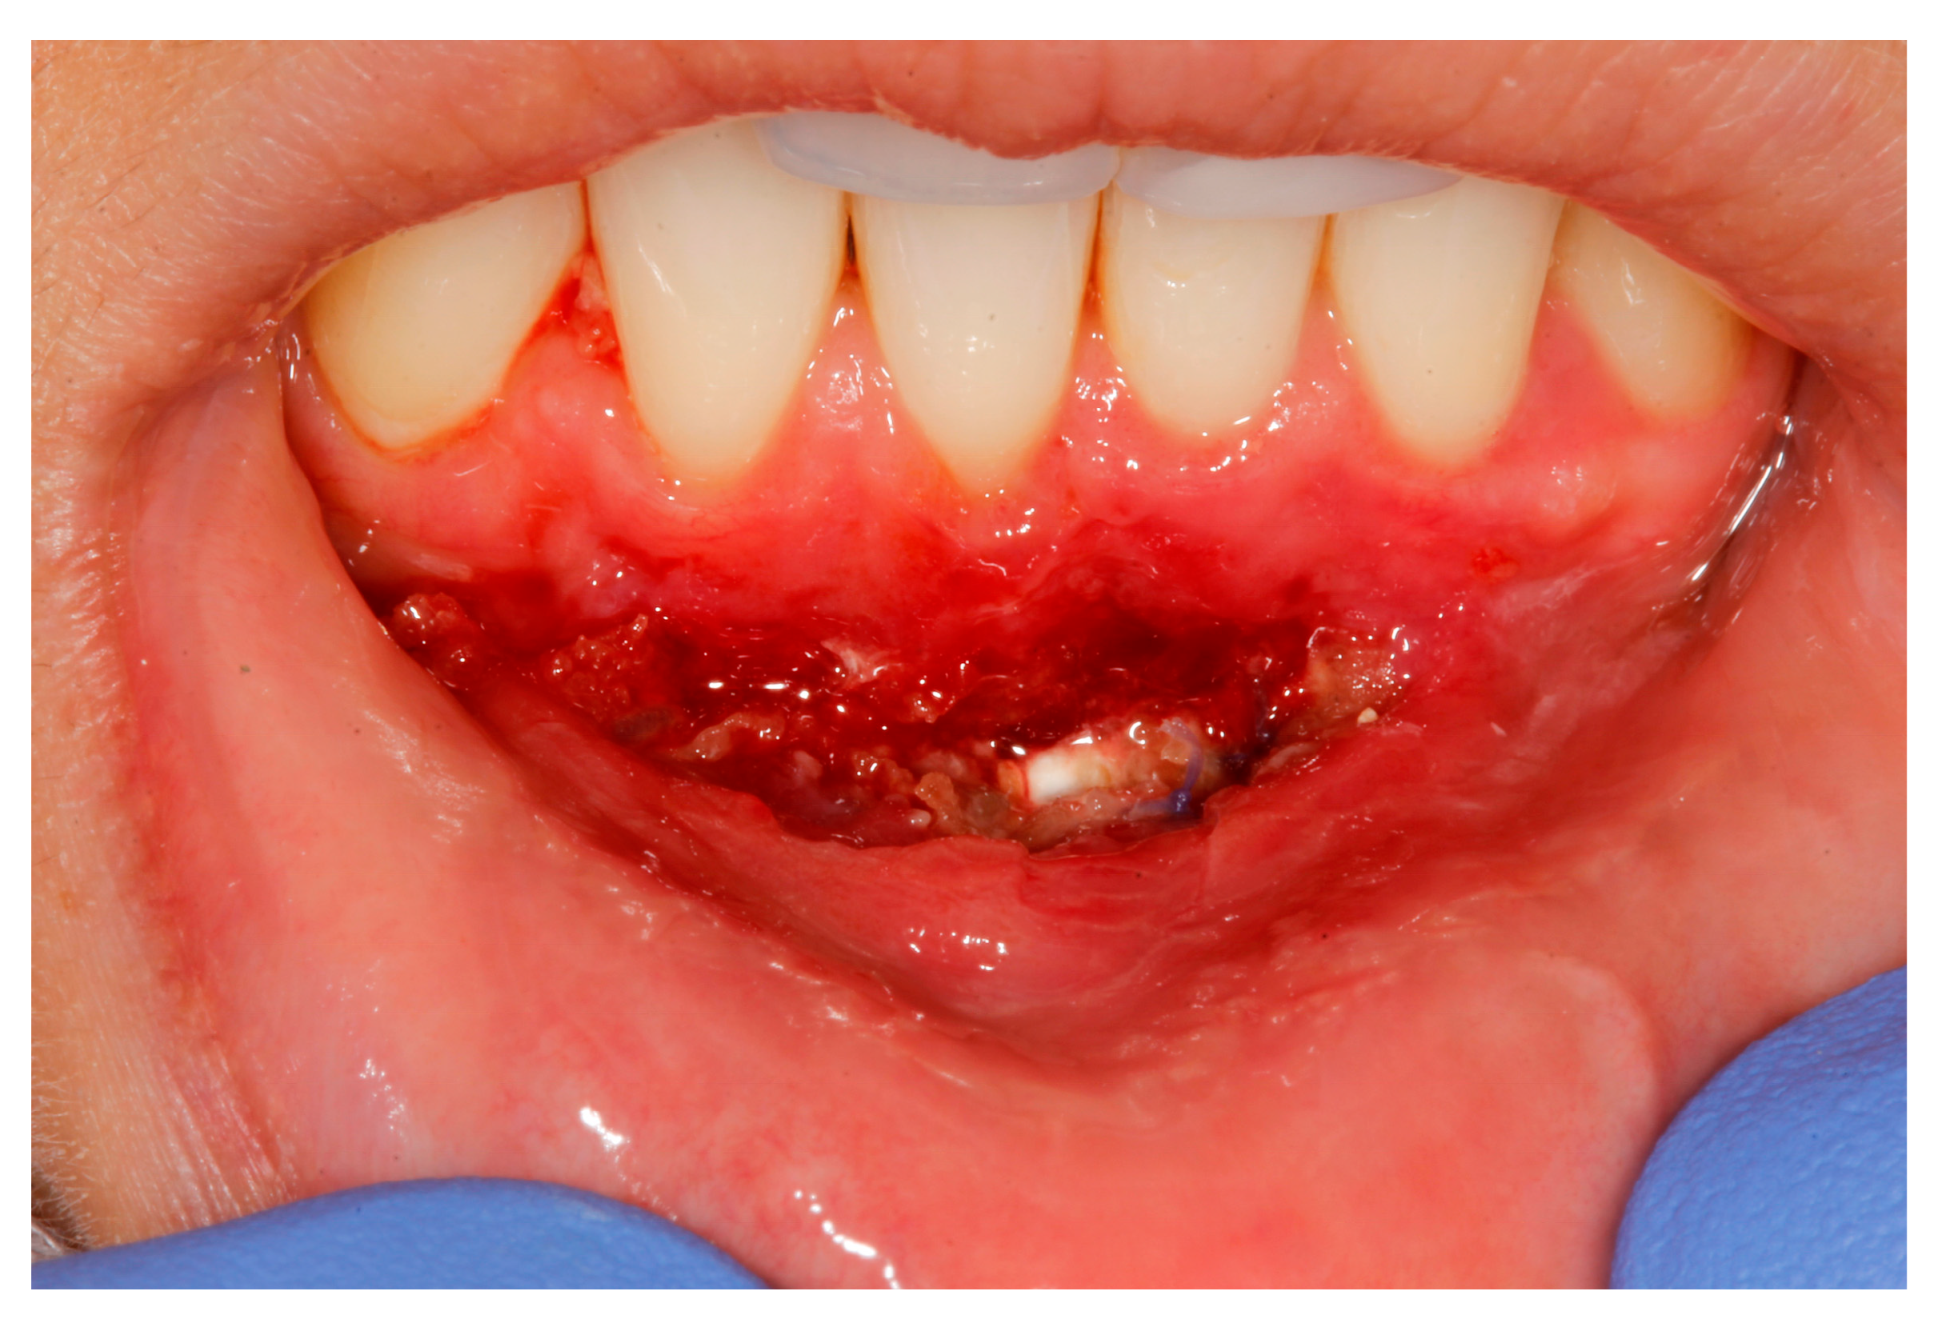

2. Case Study

- (a)

- deep partial thickness incision (blade parallel to the periosteum) made at the level of the external insertion of the frenulum;

- (b)

- elimination of superficial mucous tissue and muscle of the frenulum;

- (c)

- a series of detached points with periosteal anchorage for the apical positioning of the lining mucosa of the lip and the second intention healing of the exposed periosteum.